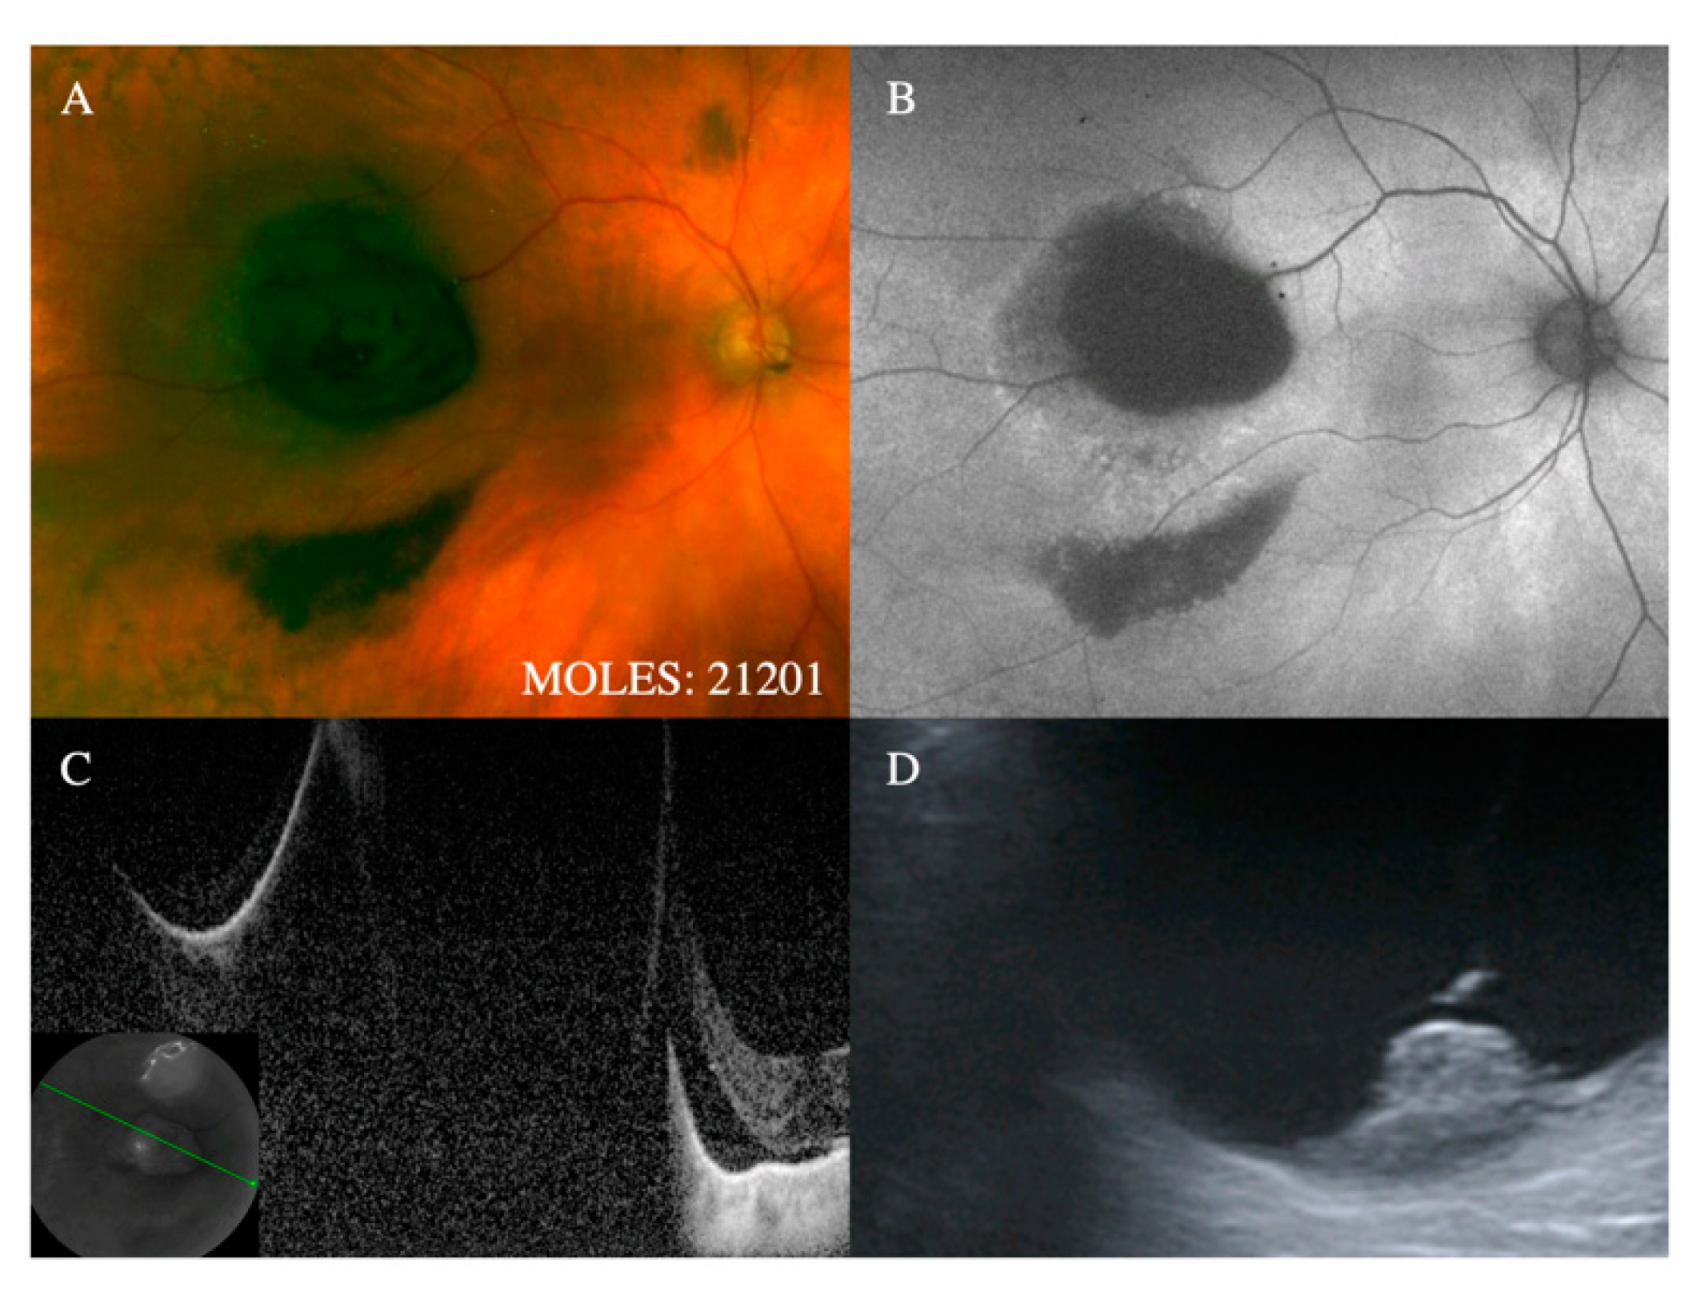

Figure 2. Representative cases demonstrating mushroom shape (i.e., M = 2). (A) Evidence of small nodule formation with associated hemorrhage on color photography and corresponding (B) hypo-autofluorescence with evidence of (C) a nodule on optical coherence tomography (OCT) and (D) confirmed on B-scan ultrasound (M = 2).

With regards to the features on which MOLES is based, the mushroom shape is almost pathognomonic for melanoma. Despite this, it is given a score of only 2 to simplify the scoring system on the assumption that tumors with this feature will have other indicators of malignancy, such as increased thickness. Occasionally, choroidal nevi can break through Bruch’s membrane to invade the retina, [18] which is why this feature is given a score of only 1. (Figure 1 and Figure 2).